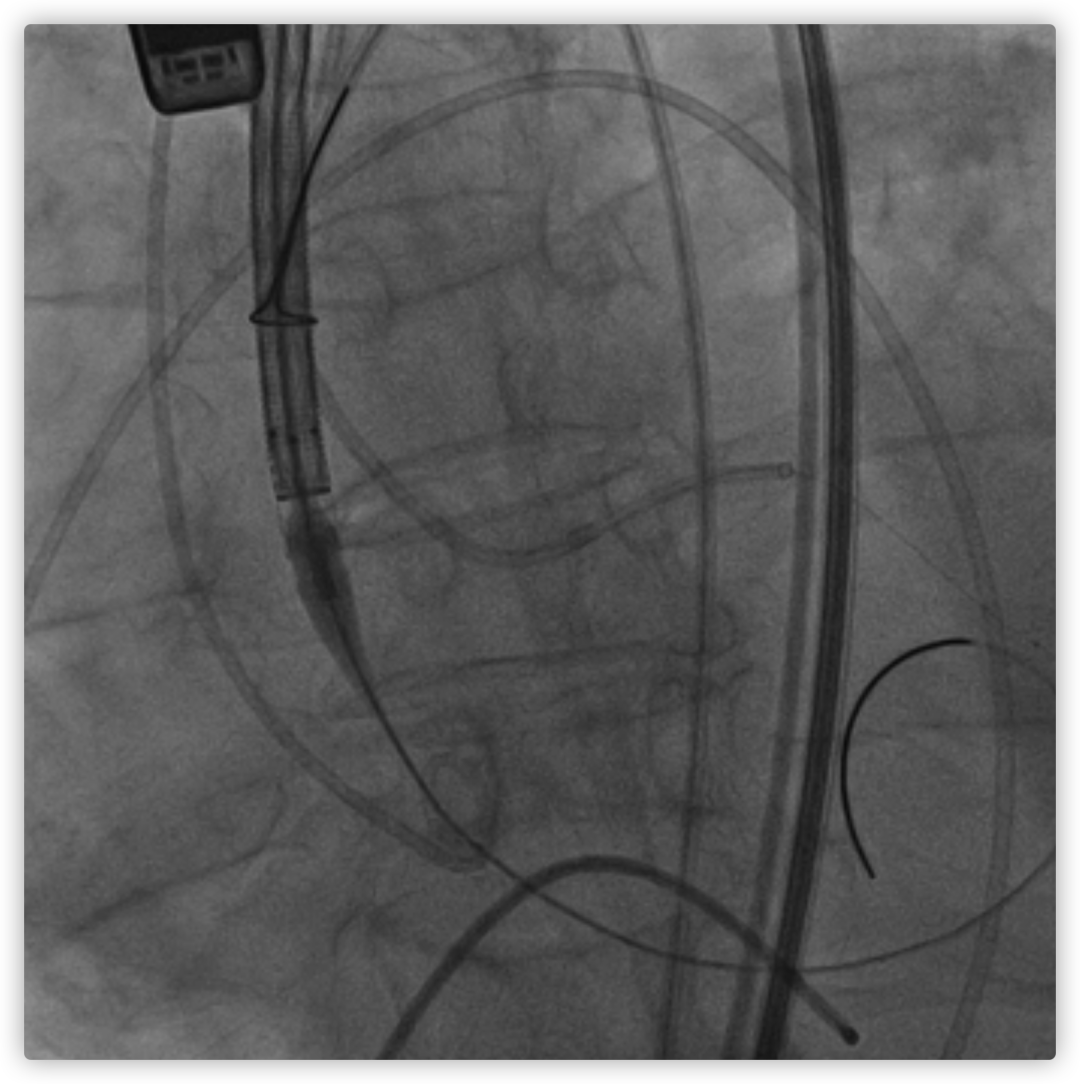

26VenusAplus+snare

瓣膜内22mm球囊后扩张,左冠无显影

LM烟囱支架植入4.0*30mm